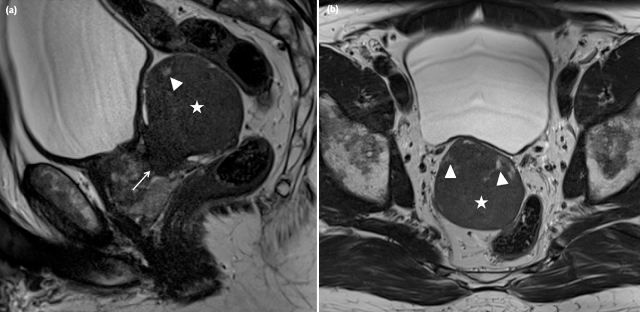

Figure 1

a) (sagittal T2w TSE) and b) (transverse T2w TSE). T2-weighted imaging showed a sharply demarcated structure (asterisk –5.8 × 6.5 × 5.2 cm) originating from the right part of the transition zone at the level of the midprostate (arrow) with massive posterior bulging The lesion was slightly T2 hyperintense relative to muscle (figure 1a and 1b), with small central T2 hyperintense areas (arrowhead).